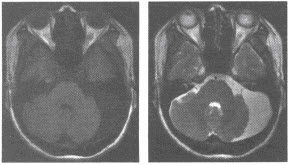

磁共振成像術(shù)的空間分辨室,也有待進(jìn)一步提高。(一)顱腦與脊髓 MRI對腦腫瘤、腦炎性病變、腦白質(zhì)病變、腦梗塞、腦先天性異常等的診斷比CT更為敏感,可發(fā)現(xiàn)早期病變,定位也更加準(zhǔn)確。

對顱底及腦干的病變因無偽影可顯示得更清楚。MRI可不用造影劑顯示腦血管,發(fā)現(xiàn)有無動脈瘤和動靜脈畸形。

MRI也叫核磁共振,MRI診斷被廣泛應(yīng)用于臨床 MRI在神經(jīng)系統(tǒng)應(yīng)用最早,也較成熟。

不僅可顯示灰質(zhì),白質(zhì),還可顯示一些神經(jīng)核,甚至可識別出腦神經(jīng),視神經(jīng)及傳導(dǎo)束。三維成像和流空效應(yīng),對病變定位不僅準(zhǔn)確,還可了解病變與血管關(guān)系,給病變定性提供診斷依據(jù)。

應(yīng)用MRI診斷顱內(nèi)原發(fā)性腫瘤和轉(zhuǎn)移瘤,顱內(nèi)感染,腦出血,腦梗塞,腦積水,腦血管畸形,脊髓和脊柱疾病具有特異性,優(yōu)于CT。對腦外傷有特異性,可檢出CT易遺漏的小血腫。